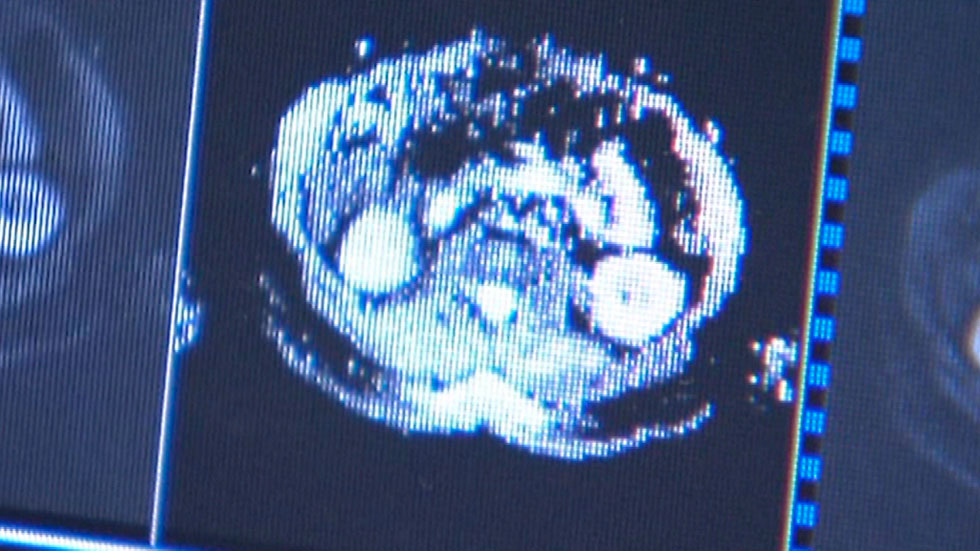

El mieloma es un tipo de cáncer de la sangre que afecta sobre todo a personas mayores de 65 años. Los últimos tratamientos han logrado ponerle cerco a la enfermedad y acercar la curación. El mieloma múltiple aparece cuando los linfocitos B, un tipo de glóbulos blancos que se localizan en la médula ósea, empiezan a reproducirse sin control. En España, se diagnostican 40 nuevos casos por cada millón de habitantes al año. Actualmente, el mieloma se controla, pero no se cura.